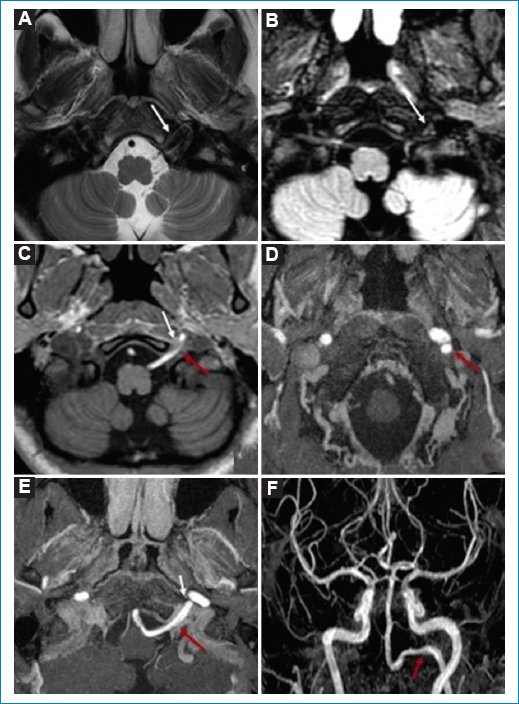

Mujer adulta joven que consulta por cefaleas, sin otros síntomas ni signos neurológicos. En la RM de encéfalo se encuentra como hallazgo positivo en las secuencias potenciadas en T2 volumétricas, la ARM 3D TOF en cortes nativos en el plano axial y en reconstrucción MIP de vasos cervicales, una estructura vascular que corresponde a la AHP, que emerge de la ACI derecha (tipo 1), con un trayecto ascendente y medial a la ACI, para unirse o finalizar en el TB atravesando el canal hipogloso del lado derecho. Las AV son hipoplásicas (Fig. 4).

Figura 4. RM de base de cráneo ponderada en T2 volumétrico (A y B), secuencia ARM 3D TOF en cortes nativos en plano axial (C), y reconstrucción MIP y 3D de vasos cervicales (D). Las figuras A, B y C muestran una estructura vascular dentro del canal hipogloso derecho que comunica con la arteria basilar (flechas rojas). Mediante la reconstrucción 3D MIP de vasos cervicales es posible identificar que esta estructura vascular corresponde a la arteria hipoglosa, que emerge de la ACI derecha (tipo 1), con un trayecto ascendente y medial a la ACI (flechas blancas), conformando el TB. Las AV son hipoplásicas.